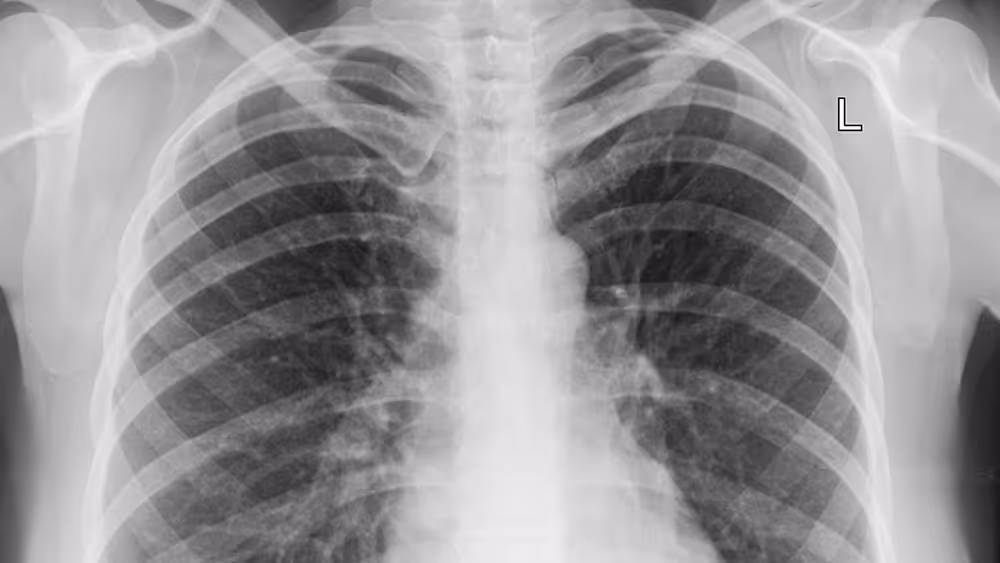

Na imagem, a bacteriana tipicamente mostra consolidação lobar ou broncopneumonia, enquanto que a viral apresenta infiltrado intersticial difuso, muitas vezes bilateral, podendo ter padrão em “vidro fosco” na tomografia.

Vale dizer que uma das pegadinhas clássicas nas provas de residência envolve quadros gripais que evoluem com piora clínica progressiva e infiltrado intersticial difuso em imagem. Se a questão enfatizar pouca ou nenhuma resposta ao uso precoce de antibióticos, pense em pneumonia viral.

Além disso, lembre-se: infiltrado bilateral e padrão em “vidro fosco” em tomografia, especialmente em épocas de surto, é pista frequente para virose respiratória.

As amostras de secreções respiratórias do nariz e da garganta devem ser colhidas até o 3º dia de sintomas, mas também o procedimento pode ser feito até o 7º dia. Já para avaliar o comprometimento dos pulmões, recomenda-se fazer um raio-x do tórax ou tomografia e para mensurar a oxigenação no sangue devem ser solicitados exames de sangue como a gasometria arterial.